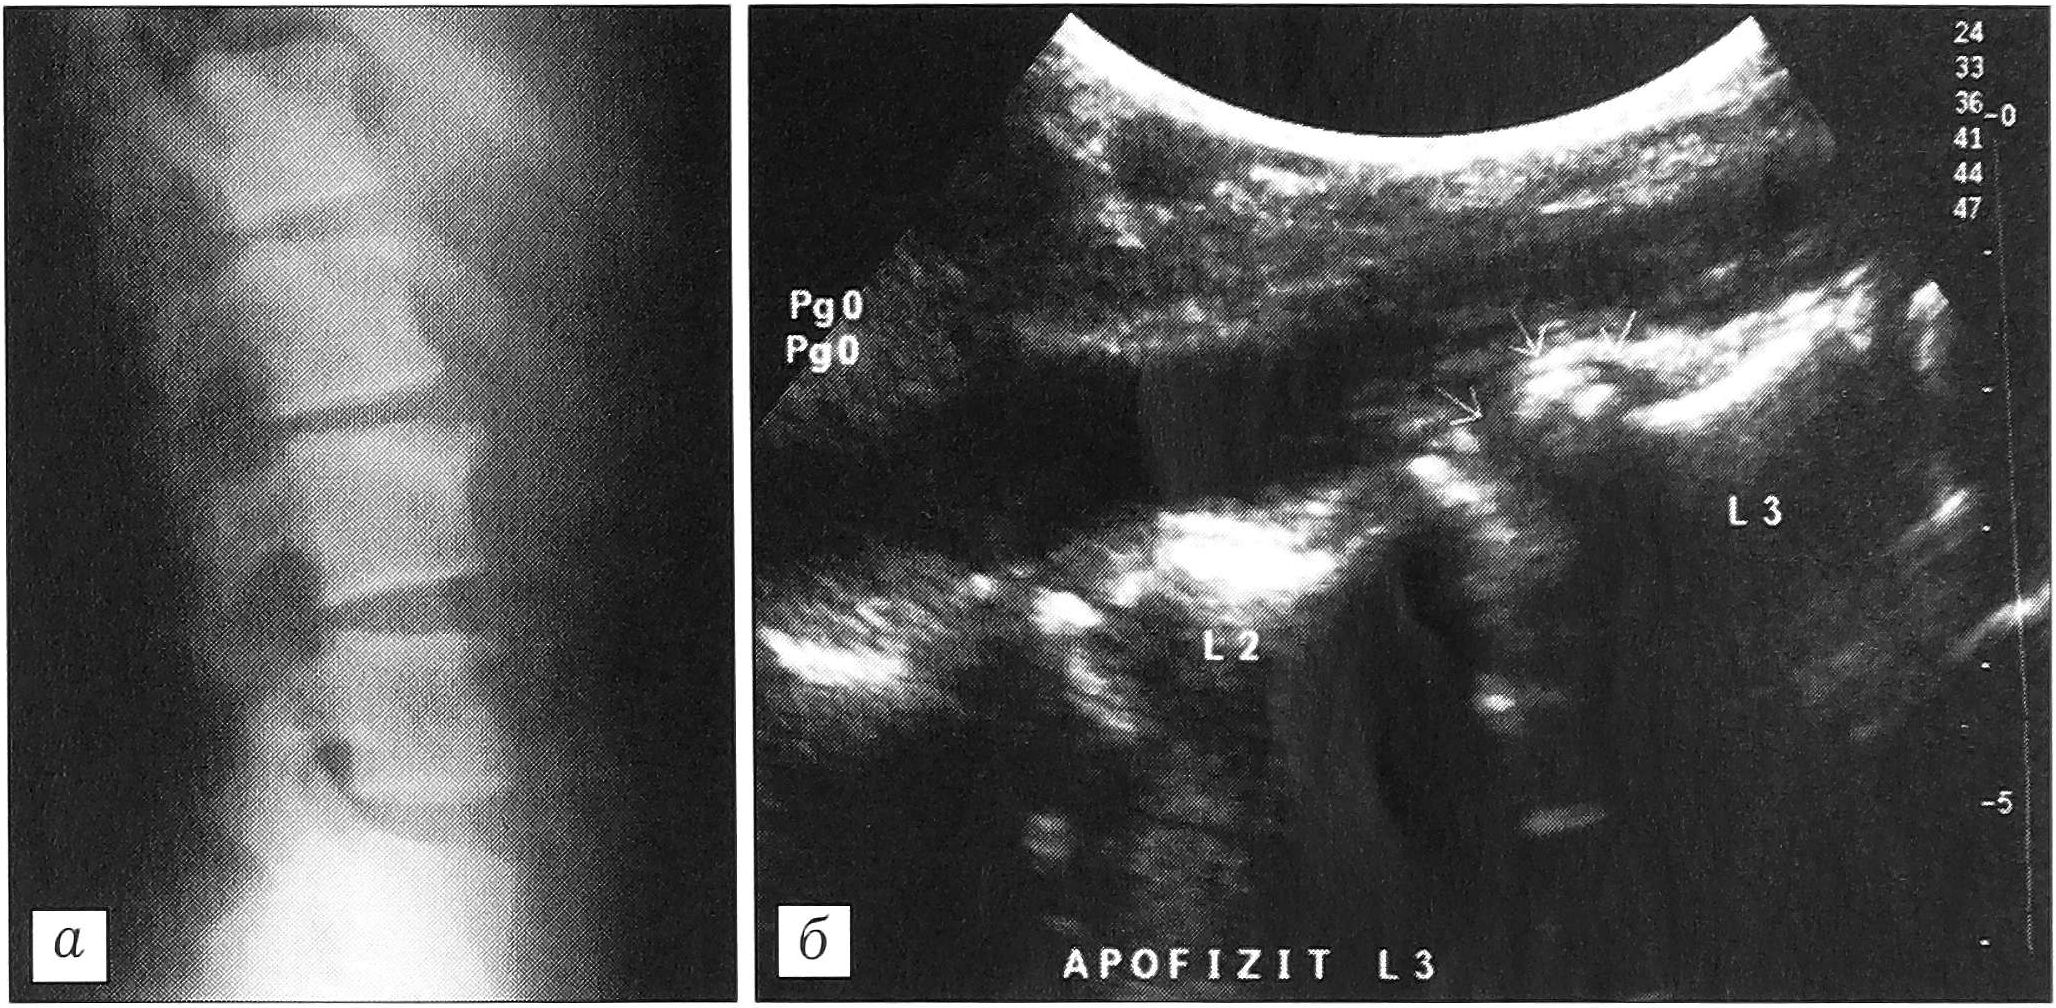

Передняя грыжа диска, апофизит. При сонографии верхнепоясничного отдела позвоночника у гимнастов, акробатов, артистов балета выявлены характерные изменения верхнего, реже переднего края позвонка (иногда двух позвонков), развившиеся в результате гиперэкстензии этого отдела позвоночника, связанной с профессиональной деятельностью. При этом апофизарное кольцо было смещено кпереди и соединялось с телом позвонка различной степени выраженности костным мостиком. Как правило, на этом уровне определялось выпячивание межпозвонкового диска кпереди — так называемая передняя грыжа диска (рис. 4). Указанные изменения лучше визуализировались при сканировании в сагиттальной плоскости. Реакция окружающих мягких тканей выражалась в отеке, разрыхлении волокнистых структур.

Рис. 4. Передняя грыжа диска L2-3, апофизит L3 позвонка. а — рентгенограмма поясничного отдела позвоночника в боковой проекции; б — ультрасонограмма той же больной: отчетливо видно разрастание фиброзной ткани в области смещенного апофиза.